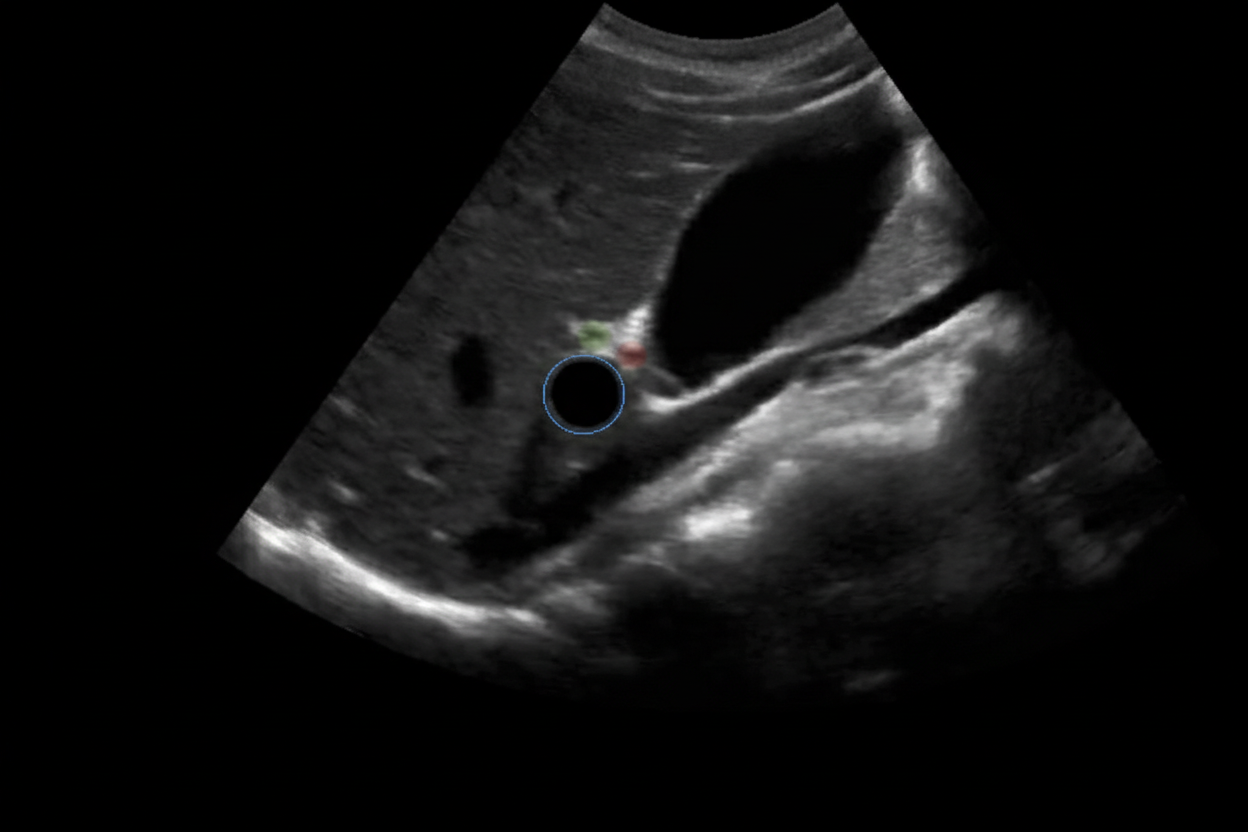

A 6-year-old baby is brought to the hospital by her parents complaining about right upper quadrant pain. On examination the baby is found to have jaundice and palpable abdominal mass. USG of the baby is shown below. What is the most likely cause?

Explanation: ***Choledochal cyst*** - The classic triad of **abdominal pain**, **jaundice**, and a **palpable right upper quadrant mass** in a child is highly suggestive of a choledochal cyst. - The ultrasound image shows a **cystic dilatation of the common bile duct** (labeled X), which is the hallmark of a choledochal cyst. *Pseudo pancreatic cyst* - Pancreatic pseudocysts usually develop after **pancreatitis** or pancreatic trauma, and are typically located in the **epigastric region**. - They are not directly associated with jaundice related to biliary obstruction, though large cysts can cause obstruction via compression. *Hydatid cyst* - Hydatid cysts are typically seen in the **liver** and are caused by *Echinococcus granulosus*, often presenting with a **multiloculated appearance** and daughter cysts. - While they can cause hepatomegaly and pain, jaundice and a palpable mass, they do not typically manifest as a primary dilatation of the bile duct. *Amoebic liver abscess* - An amoebic liver abscess is caused by *Entamoeba histolytica* and typically presents with **fever**, **right upper quadrant pain**, and sometimes hepatomegaly. - While it can cause biliary obstruction in rare cases, the ultrasound appearance is usually that of a **hypoechoic lesion** within the liver parenchyma, not a distinct cystic dilatation of the bile duct. *Biliary atresia* - Biliary atresia typically presents in **early infancy** (first 2-3 months of life) with progressive jaundice and acholic stools. - While it causes biliary obstruction, the ultrasound findings show **absent or atretic bile ducts** rather than cystic dilatation, and the age of presentation (6 years) makes this diagnosis unlikely.